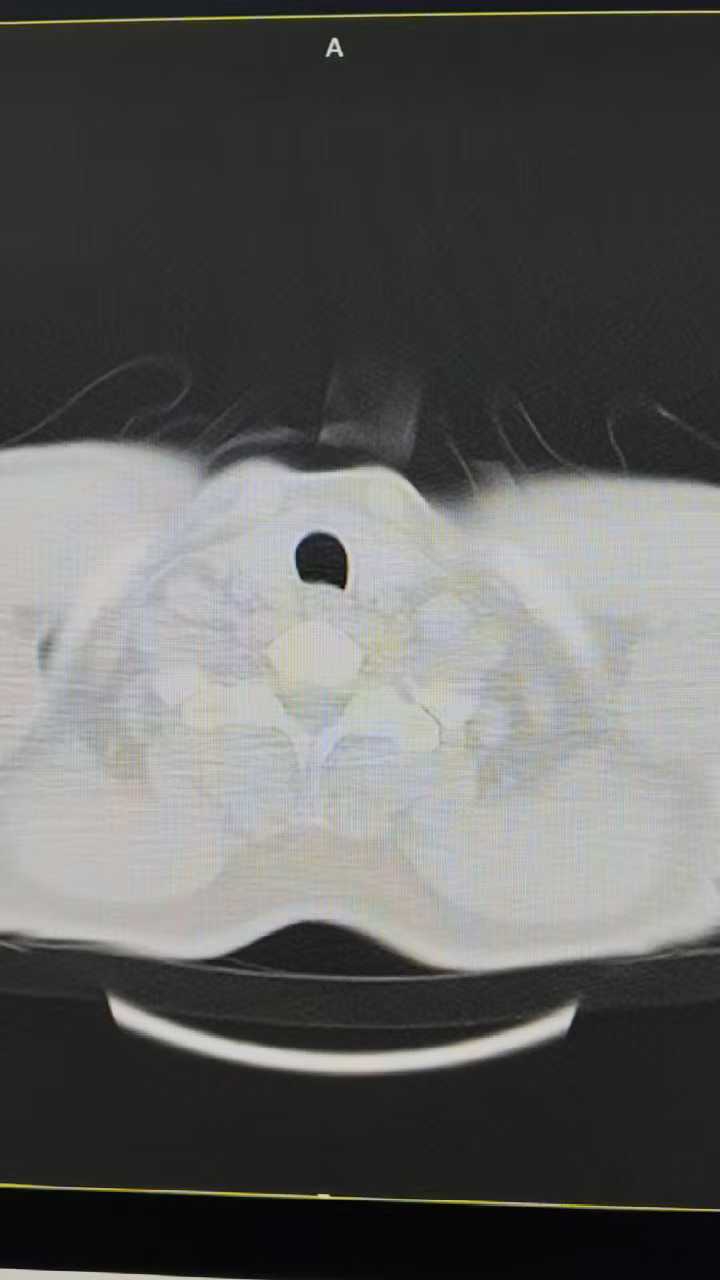

这时候我们再看看患者的ct像

两肺间质性改变,铺路石征。答案已经呼之欲出了,没错这就是 肺泡蛋白沉积症(PAP)